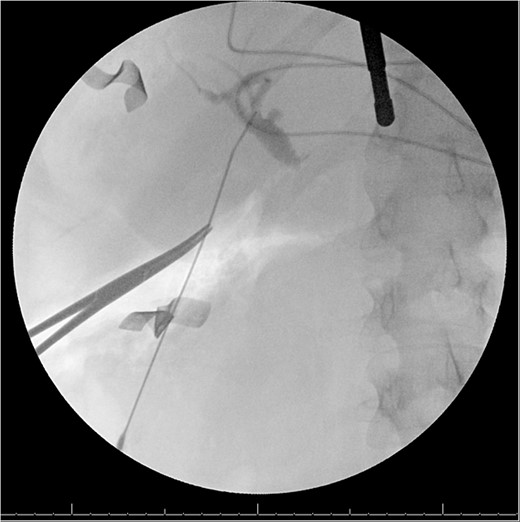

A 49-year-old female with a history of ADPKD and multiple liver cysts, 13-months status post subtotal cholecystectomy, endoscopic retrograde cholangiopancreatography with biliary sphincterotomy and balloon stone extraction, presented to the emergency department with fever and a 4-day history of discomfort in the right upper quadrant. At the time of the initial cholecystectomy, total cholecystectomy could not be performed due to extensive adhesions, and subtotal cholecystectomy with complete evacuation of the stones was done instead. Magnetic resonance cholangiopancreatography (MRCP) done at that time showed a dilated common bile duct (CBD) to 1.5 cm, intra and extrahepatic biliary dilatation, multiple liver cysts measuring up to 2 cm, and multiple stones in the CBD, including at the level of the ampulla (Fig. 1). Computerized tomography scan at the time of the second admission showed acute cholecystitis and she had mildly elevated transaminases, but there was no evidence of cholestasis or pancreatitis. MRCP showed minor proximal intrahepatic biliary dilation and cholelithiasis but no duct calculi (Figs 2–4). A laparoscopic cholecystectomy was attempted with extensive adhesiolysis between the gallbladder and surrounding omentum and mesocolon, but the cystic duct could not be isolated, and ultimately the cased was converted to open. While removing the gallbladder in a top-down fashion, a small bile leak was identified right at the closed end of the gallbladder remnant, where the bile duct was adhered to the gallbladder wall. Intraoperative cholangiogram was obtained through a small perforation in a right posterior bile duct at the site of attachment, which showed right posterior, right anterior and left hepatic ducts of equal size converged at a trifurcation (Fig. 5). The duct was repaired over a T-tube and observed throughout the rest of the case and no bile leak was identified. The gallbladder was opened along its lateral edge, revealing a hugely dilated cystic duct with ~10 to 12 marble-sized stones packed within the gallbladder remnant and cystic duct down to the juncture with the common bile duct. All the stones were removed and the safe portion of the gallbladder remnant was resected leaving the side attached to the bile duct in situ due to the Mirizzi anatomical variant. The cystic duct was oversewn along with the remnant of the gallbladder wall. Pathology showed acute-on-chronic cholecystitis with cholelithiasis. Repeat MRCP showed no retained stones in the biliary tree. The recovery course was unremarkable.

MRI/MRCP from second hospitalization demonstrating recurrent cholelithiasis.